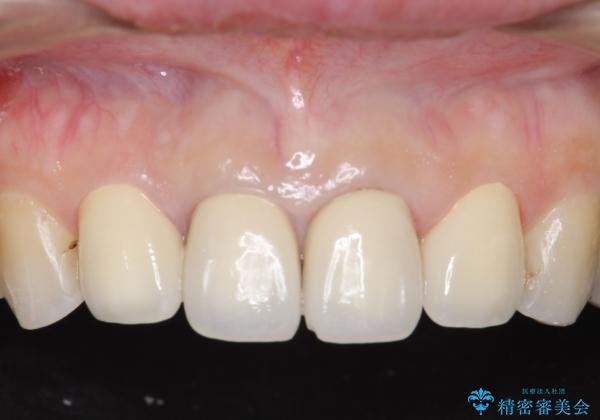

- 上顎の前から2番目の歯の古い樹脂をセラミックにしたいといらっしゃった方の症例です。

古い樹脂を除去後、オールセラミッククラウンによる補綴を行いました。

- オールセラミッククラウン…¥100,000×2、仮歯…¥10,000×2費用は治療当時の料金となります

今回用いたオールセラミッククラウンはジルコニアフレームという白い素材の上にセラミックを盛っているため、審美性が非常に高いのが特徴です。

また、ジルコニアは人工ダイヤモンドの材料にも使われているほど高い強度を持っており、そのためオールセラミッククラウンは審美性だけでなく、奥歯やブリッジの補綴も可能とするクラウンです。